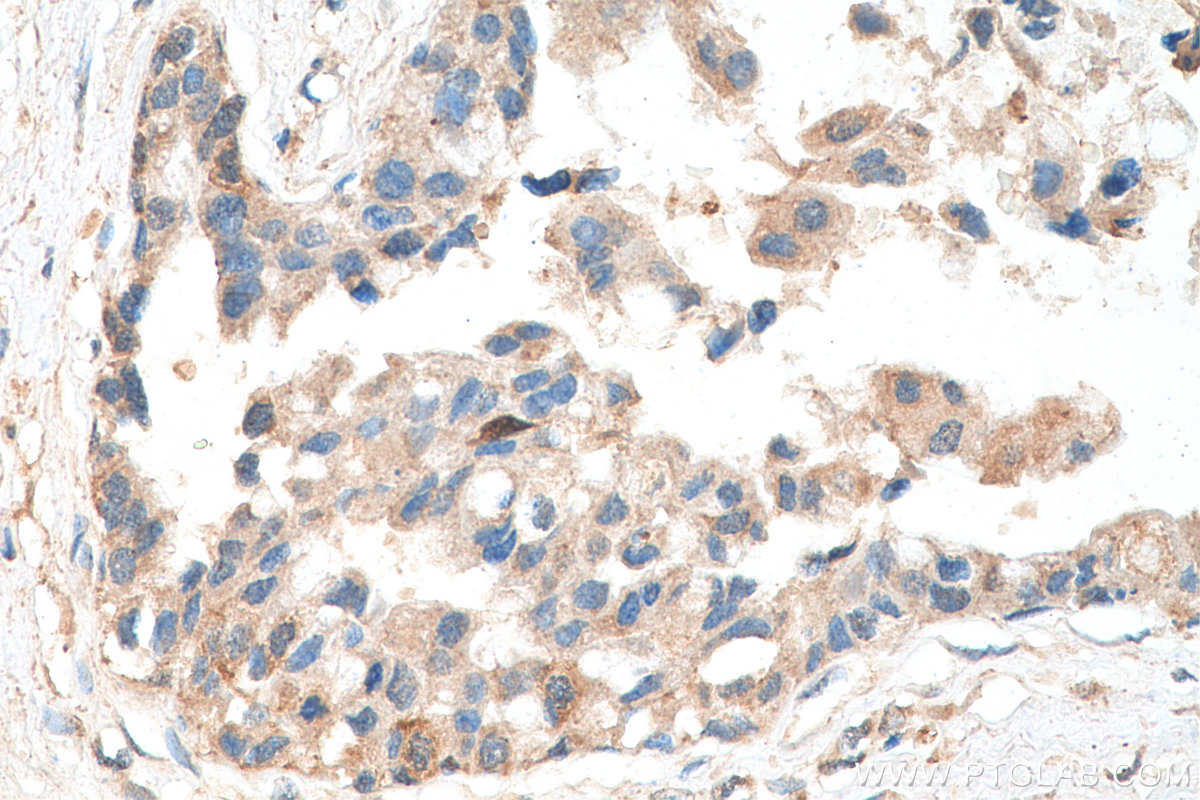

| Positive IHC detected in | human breast cancer tissue Note: suggested antigen retrieval with TE buffer pH 9.0; (*) Alternatively, antigen retrieval may be performed with citrate buffer pH 6.0 |

| Immunohistochemistry (IHC) | IHC : 1:50-1:500 |